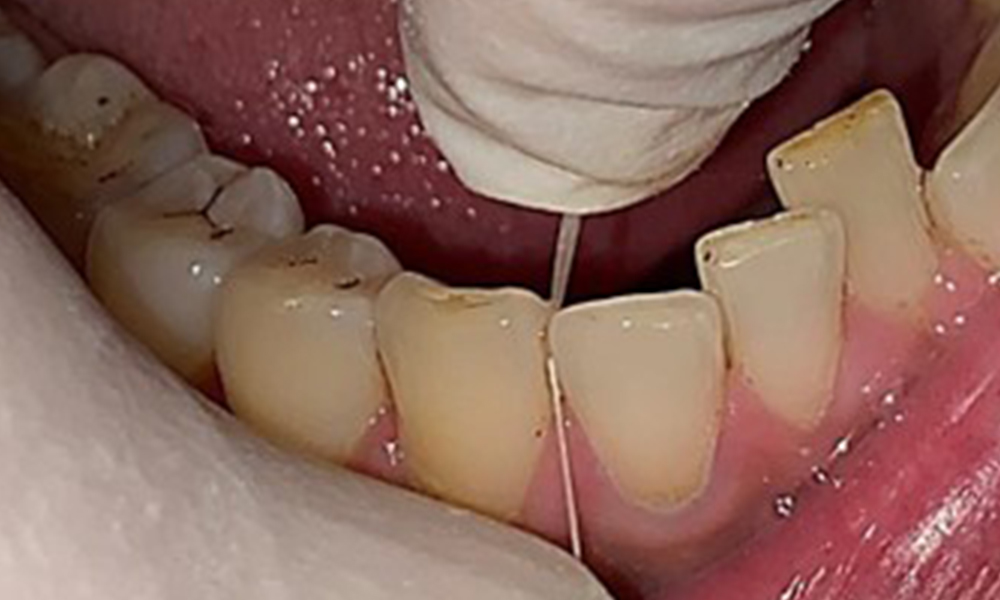

Oferirea de sfaturi cu caracter de instruire, precum și încercările de creștere a motivației pacientului sunt componente importante ale acestor întâlniri în cabinet. De asemenea, buna înțelegere a igienei orale și o conduită adecvată la domiciliu sunt aspecte esențiale pentru pacienți. Acumularea de placă dentară este evidentă în special în zonele cervicale (fig. 8).

Acestea aspecte trebuie discutate în detaliu cu pacientul și în vederea eventualei necesități de îmbunătățire a tehnicii de spălare a dinților. Prezența eroziunilor și a atrițiilor indică recomandarea de utilizare a unei periuțe de dinți cu peri moi, pentru igiena orală la domiciliu.

De asemenea, este necesar să se verifice dacă periuțele interdentare - pe care acest pacient le folosește zilnic - sunt de dimensiune corectă și să se încurajeze utilizarea lor cu consecvență (fig. 9). O bună igienă orală minimizează semnificativ riscul de parodontoză cauzată de fumat.